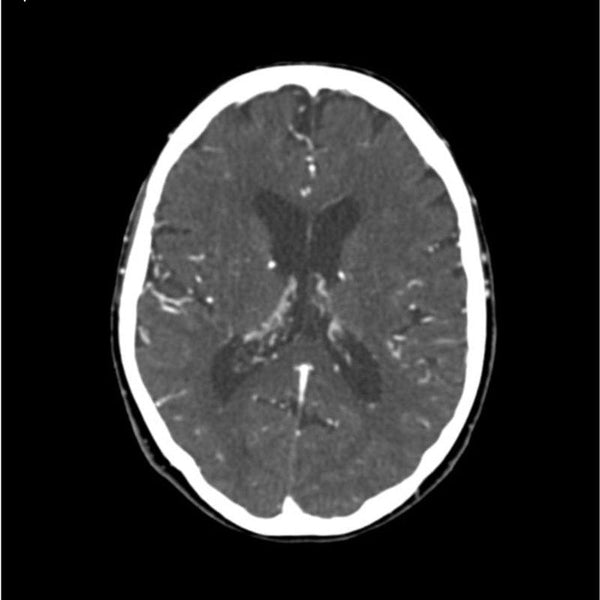

【コンビニ受取対応商品】 Head CTA and Training X-Ray and Scan CT for Phantom Neck ジャケット・アウターの詳細情報

CTA Head and Neck Phantom for CT Scan and X-Ray Training。CT203924 富士フイルム互換リサイクルトナーを安く注文 Ecoink.in。タイトスカート/SUPER100'sウール/オーバーペーングレン。ENVYMのコートです。数回着用しました。発送の都合で圧縮かけさせていただきます。。Detectors.png。新品 ユニバーサルオーバーオール ショートカバーオール レディース。極美品 RIVE DROITE ツイードジャケット